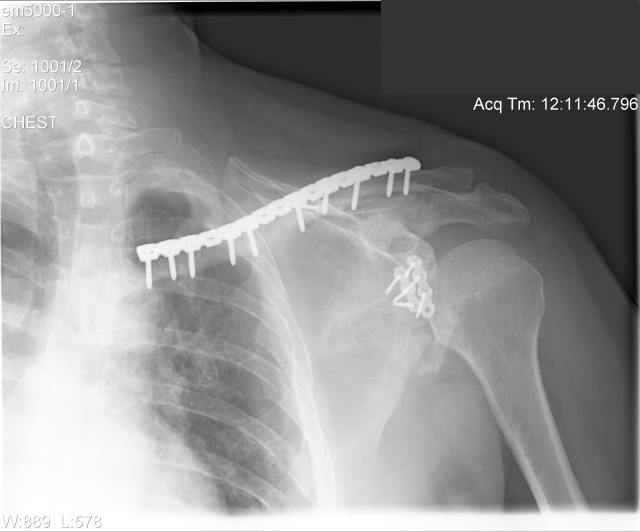

See if you find all 17 screws. One's sideways.